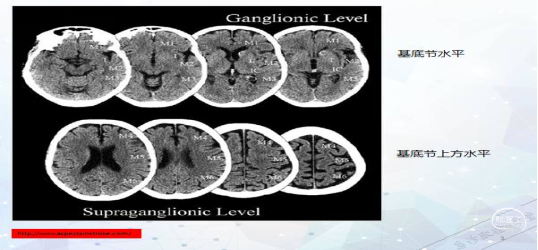

1、前循环ASPECT评分

大脑中动脉(middle cerebral artery,MCA)供血区2个层面的10个区域:

①核团层面(即丘脑和纹状体平面),分为M1、M2、M3、岛叶、豆状核、尾状核和内囊后肢7个区域;

②核团以上层面(在核团水平上2cm),包括M4、M5 和M6。

两者的界限为尾状核头部:

任何位于尾状核及其以下层面的缺血性改变为核团层面,

在尾状核头部层面以上的缺血性改变为核团上层面。

各区域都为1分

评分时从10分中减去存在相应的区域数目,10分代表CT平扫正常,0分表示MCA供血区广泛缺血。